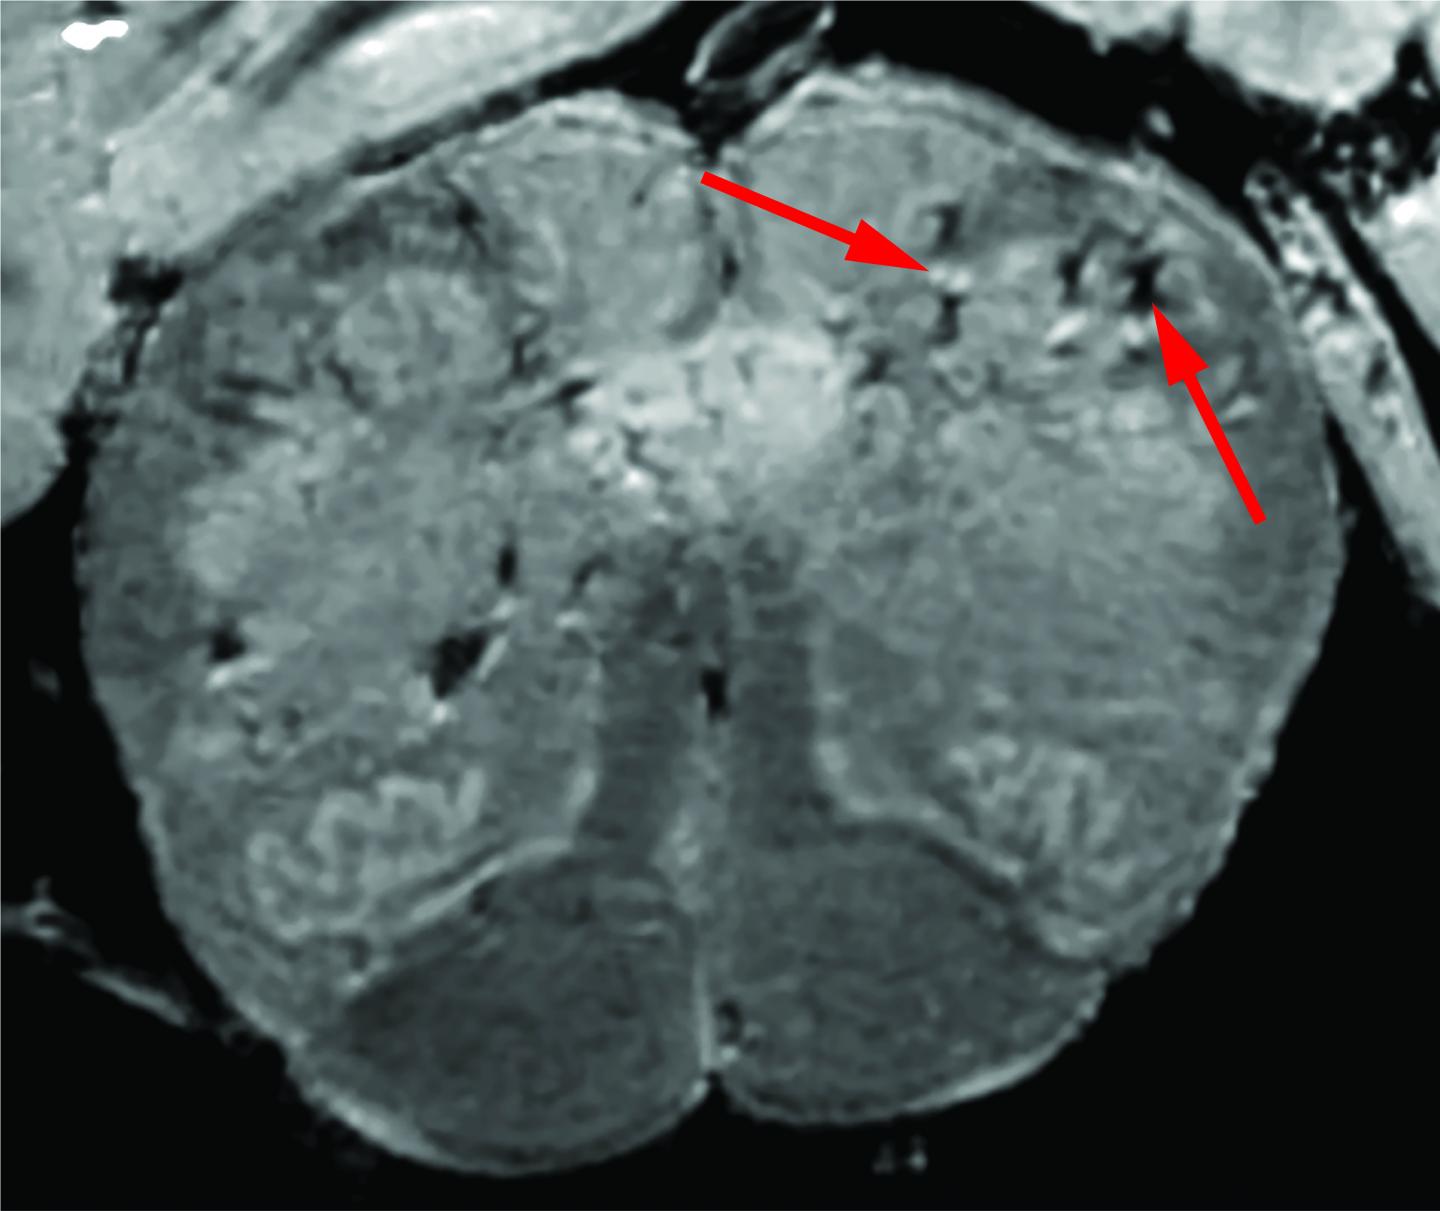

image: In an in-depth study, NIH researchers consistently found blood vessel damage in the brains of COVID-19 patients but no signs of SARS-CoV-2 infections. Here is a high-resolution scan of a patient's brain stem. Arrows point to light and dark spots that are indicative of blood vessel damage observed in the study.

Initially, the researchers used a special, high-powered magnetic resonance imaging (MRI) scanner that is 4 to 10 times more sensitive than most MRI scanners, to examine samples of the olfactory bulbs and brainstems from each patient. These regions are thought to be highly susceptible to COVID-19. Olfactory bulbs control our sense of smell while the brainstem controls our breathing and heart rate. The scans revealed that both regions had an abundance of bright spots, called hyperintensities, that often indicate inflammation, and dark spots, called hypointensities, that represent bleeding.

The researchers then used the scans as a guide to examine the spots more closely under a microscope. They found that the bright spots contained blood vessels that were thinner than normal and sometimes leaking blood proteins, like fibrinogen, into the brain. This appeared to trigger an immune reaction. The spots were surrounded by T cells from the blood and the brain's own immune cells called microglia. In contrast, the dark spots contained both clotted and leaky blood vessels but no immune response.